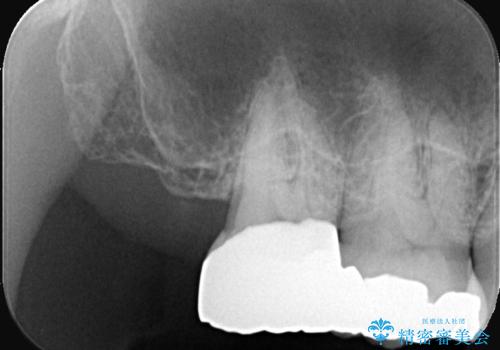

今回も不適合な銀歯を外したらその下は虫歯になっていました。

虫歯を除去後、フルジルコニアクラウンで治療を行いました。

不適合な銀歯を外して、虫歯の除去後にシリコンで印象をとりフルジルコニアクラウンで治療を行いました。